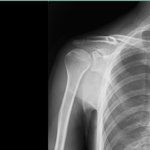

○ 鎖骨骨折

10代の鎖骨骨折は驚くほど早く治ります。骨がずれていてもしっかりと新しい骨が広がり、しかも屈曲していた骨は成人になるまでに自家矯正し過去に骨折した形跡が分からないほどになります。

病院ではメスを入れプレートやビスで止める手術がありますが、手術痕は一生取れません。

バスケットボール部に所属する彼は肩から転び骨折しましたが、2週間もすると骨折した部分の圧痛もやわらぎ1か月半で復帰しました。若く代謝もよいので毎日体を清拭して、きれいな下着に着替えさせました。もちろん包帯も固定具も洗濯し毎日気持ちよく過ごせるようにしました。